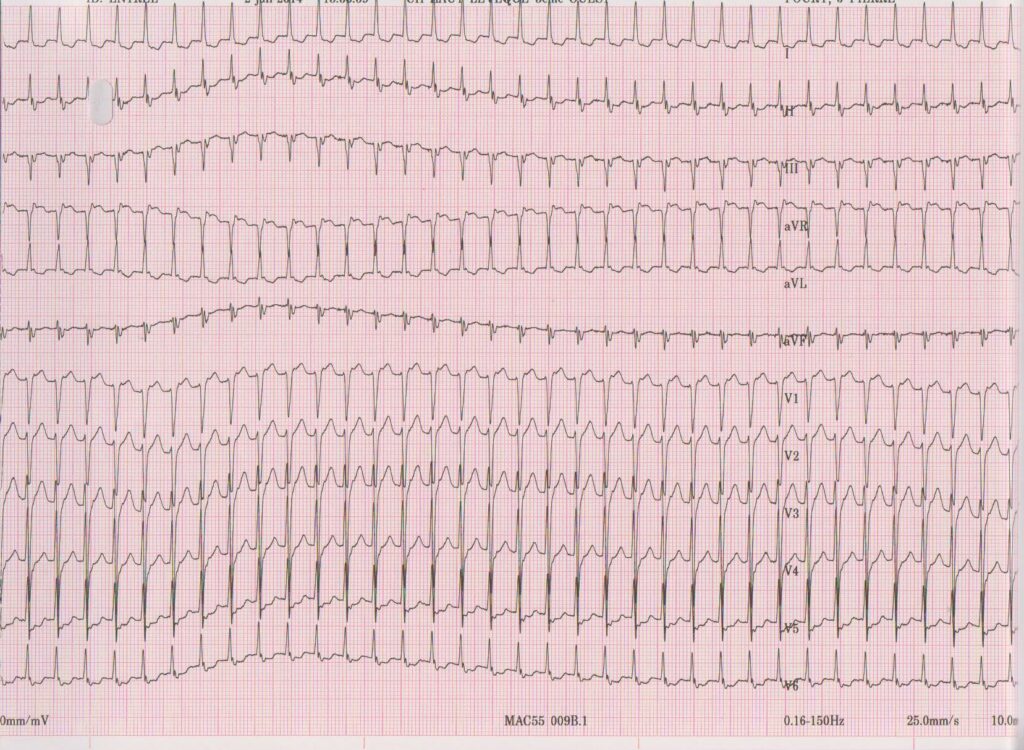

• La fréquence de la tachycardie peut varier d’un patient à l’autre (entre 130 à 250 bpm); elle est généralement très rapide chez l’enfant (> 200 bpm) et plus lente chez les personnes âgées (< 150 bpm) quand la conduction nodale est altérée;

• Les QRS sont fins dans la majorité des cas, même si une aberration de conduction est possible; une alternance des QRS peut être observée sans être spécifique;

• Conduction auriculo-ventriculaire 1/1; les ondes P’ sont rétrogrades et peuvent se superposer à la partie terminale du QRS; elles sont alors difficilement identifiables; la primo-dépolarisation atriale est antéro-supérieure (à l’émergence de la voie rapide); elles peuvent modifier la morphologie du QRS (en comparaison avec les complexes d’origine sinusale) avec un aspect caractéristique de pseudo-onde S dans les dérivations inférieures et de pseudo-onde r’ (discret retard droit) en V1 ou en aVR; plus rarement, l’activité atriale peut être positionnée juste avant le QRS; certains aspects électrocardiographiques sont moins typiques avec un bloc de conduction antérograde et 2 activités atriales pour un ventricule;

Description tracé